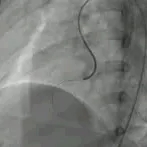

首次术中影像

建立股动脉-VSD-股静脉轨道,沿泥鳅导丝送7F输送鞘至左室,患儿血压由90/50mmHg降至55/30mmHg,心率由100次/分升至120次/分左右,立即药物升压后血压不稳定,撤出导管后血压恢复至95/60mmHg,超声监测到右侧房室沟极少量心包积液2mm,随送入输送鞘管过程,心包积液游走于右侧房室沟-左侧心室侧壁,送入鞘管后血压下降心率增快,撤出鞘管后血压回升心率下降,反复3-4次相同情况,遂终止手术。